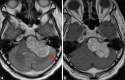

Schwannomas are benign soft-tissue tumors that arise from peripheral nerve sheaths throughout the body and are commonly encountered in patients with neurofibromatosis Type 2. The vast majority of schwannomas are benign, with rare cases of malignant transformation reported. In this pictorial review, we discuss the magnetic resonance imaging (MRI) appearance of schwannomas by demonstrating a collection of tumors from different parts of the body that exhibit similar MRI characteristics. We review strategies to distinguish schwannomas from malignant soft-tissue tumors while exploring the anatomic and histologic origins of these tumors to discuss how this correlates with their imaging findings. Familiarity with the MRI appearance of schwannomas can help aid in the differential diagnosis of soft-tissue masses, especially in unexpected locations.